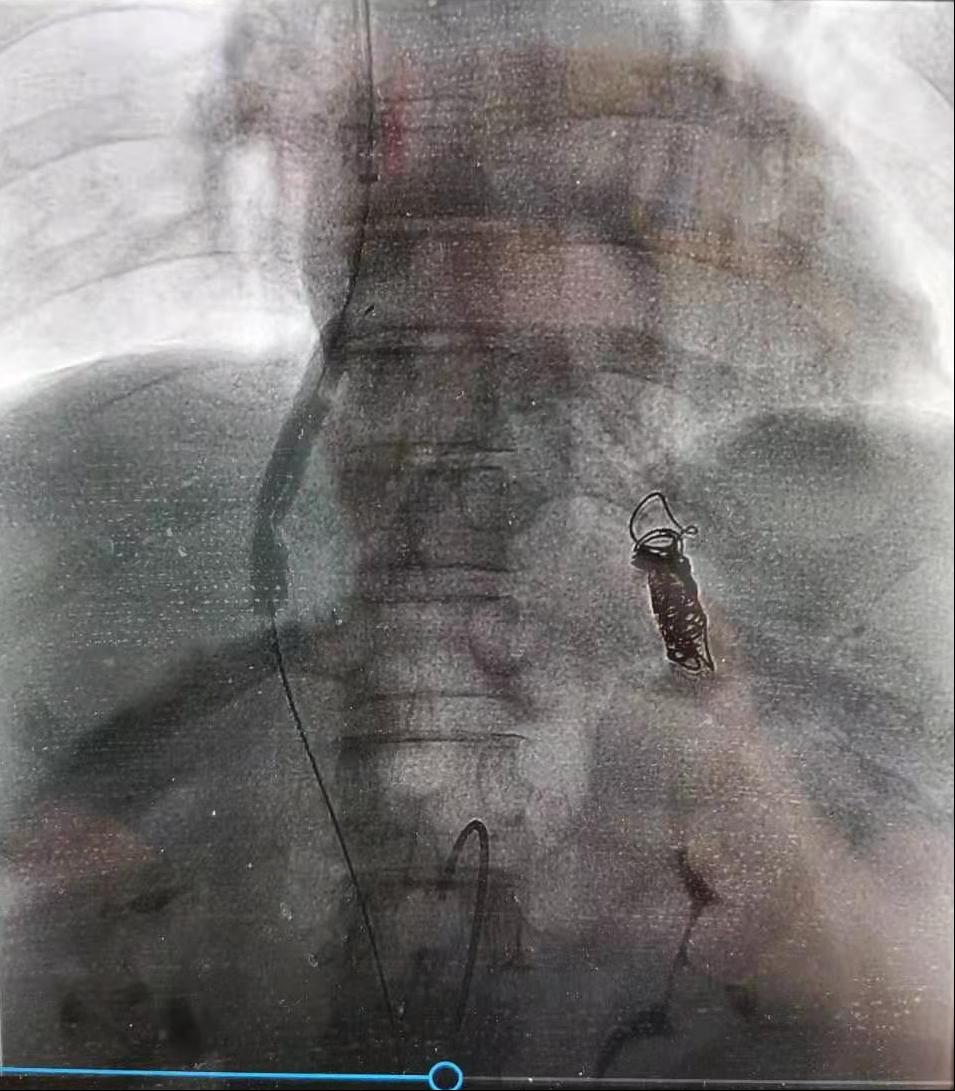

为预防患者再次出血,解决门静脉高压,消化内科医护人员经讨论后决定行TIPS术治疗。8月10日,在院领导及介入科、心内科、普外科等相关科室大力支持下,消化内科王宇晖主任、赵新功副主任医师、王亚茹护士长、常月红主管护师等组成的手术团队,在介入科顺利完成了间接门静脉造影术、TIPS支架置入术、胃冠状静脉栓塞术及脾胃肾分流道封堵术。术后患者恢复良好,第二天即可下地活动。术后复查TIPS支架通畅,第四天患者出院。

TIPS手术(经颈内静脉肝内门体静脉分流术)是治疗肝硬化失代偿期食管胃底静脉曲张出血的一把利器,是解决肝硬化失代偿期上消化道大出血最直接、有效的治疗手段。该手术可以解决患者反复出血、难治性腹水及根本上解决门脉高压问题,但因手术难度大,技术要求高,目前在我国仅少数医院开展,在陕西省能够开展的医院屈指可数。消化内科TIPS手术的开展,为渭南市肝硬化失代偿期患者带来更多生的希望,也将医院消化介入诊疗技术带入全省先进行列。